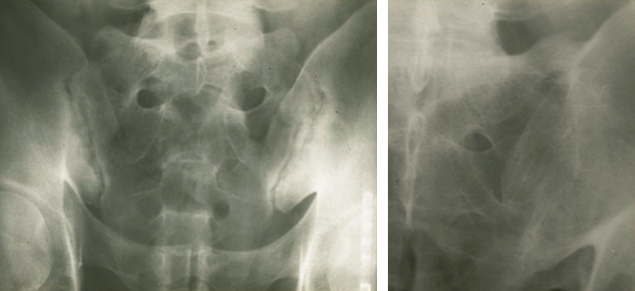

What is the difference b/t these two images?

What do you see here?

What are the x-ray findings with AS?